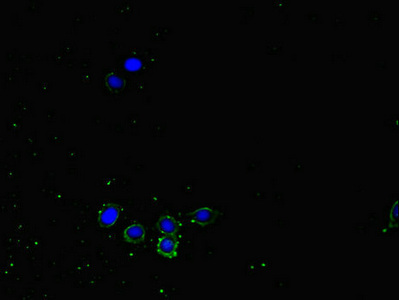

Immunofluorescent analysis of HepG2 cells using CSB-PA016092LA01HU at dilution of 1:100 and Alexa Fluor 488-congugated AffiniPure Goat Anti-Rabbit IgG(H+L)